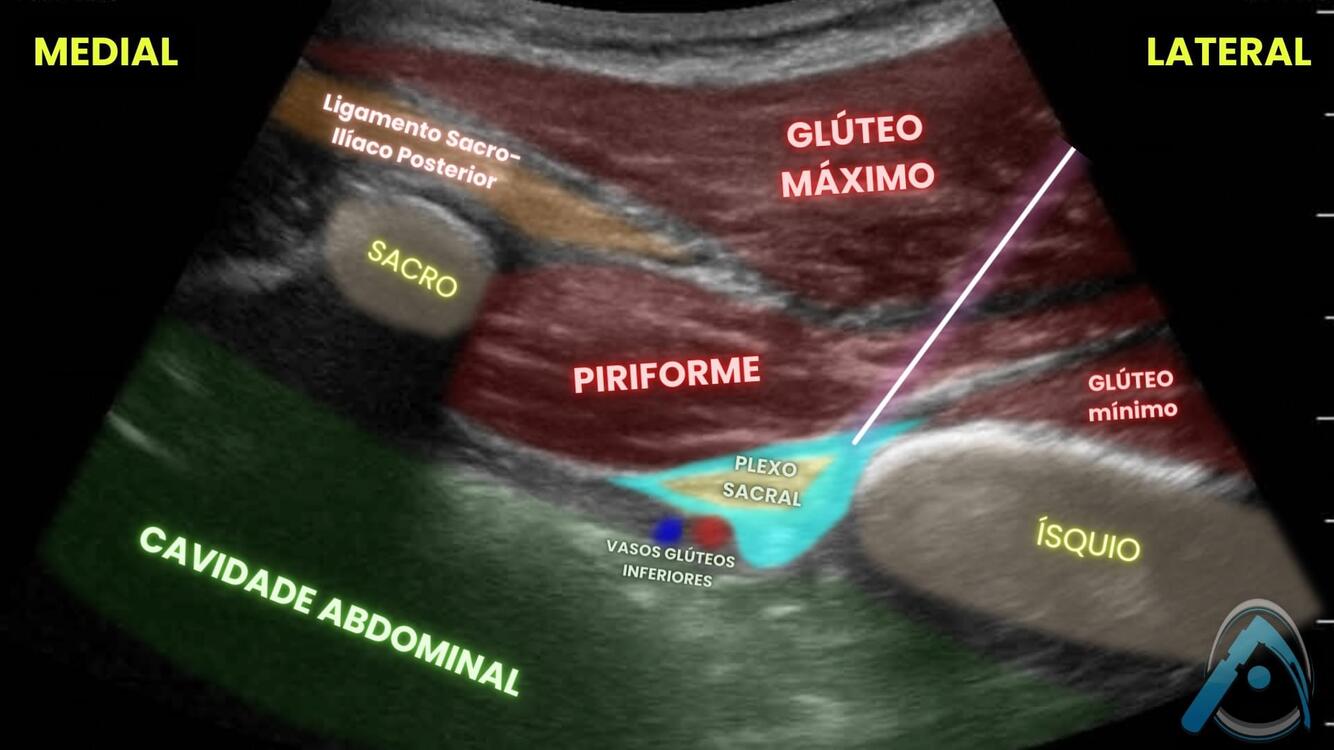

Você já viu o bloqueio do plexo sacral guiado por USG? Identifique as estruturas em destaque:

A

1 - glúteo máximo;

2 - piriforme;

3 - plexo sacral